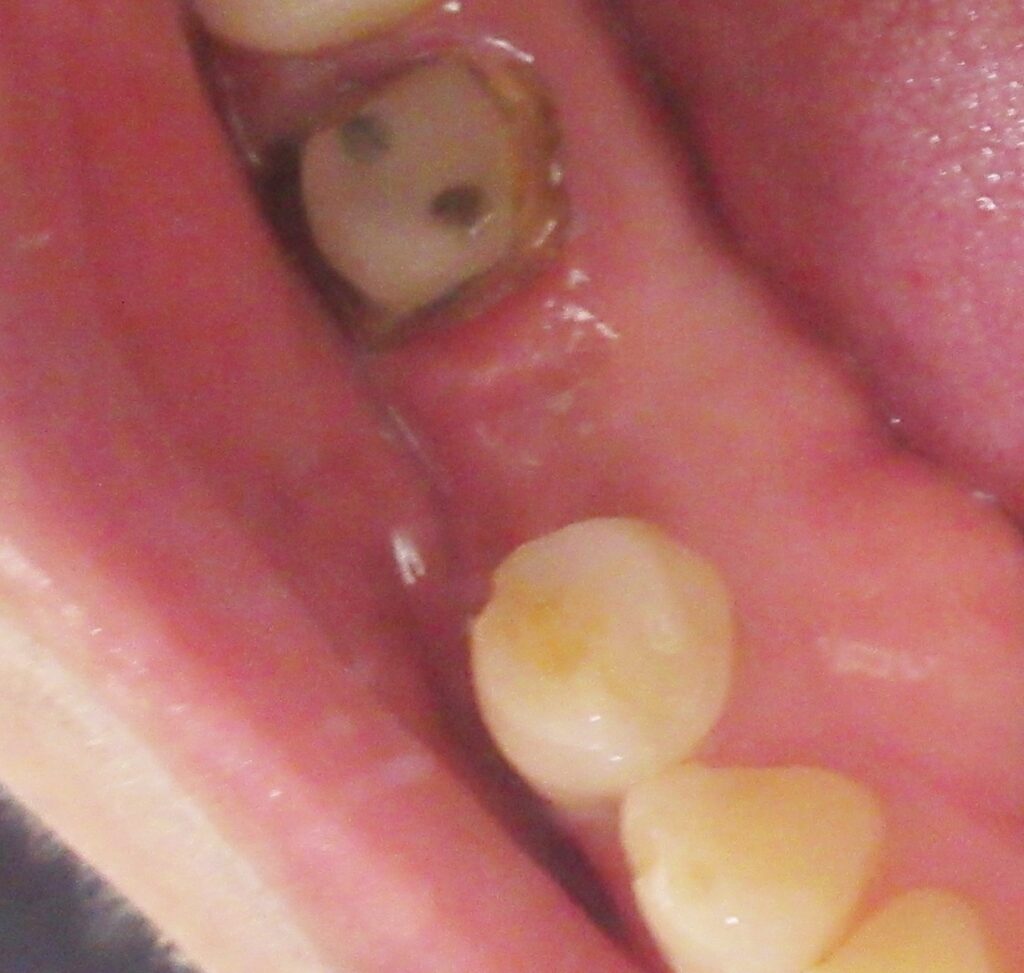

今回の患者様はインプラント植立を希望され、右下5番目の植立が決まりました。

当日の様子は、まず診療室に入っていただき、簡単にお口の中の全体的なお掃除と麻酔、仮歯を外す処置、CGFのための採血を行います。